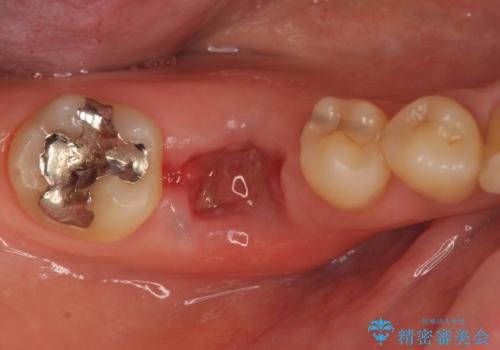

被せ物を外したところ、歯が大変薄くなって割れており、残念ながら残すことはできないと説明しました。

歯がなくなったところに関しては、ブリッジで修復することにしました。